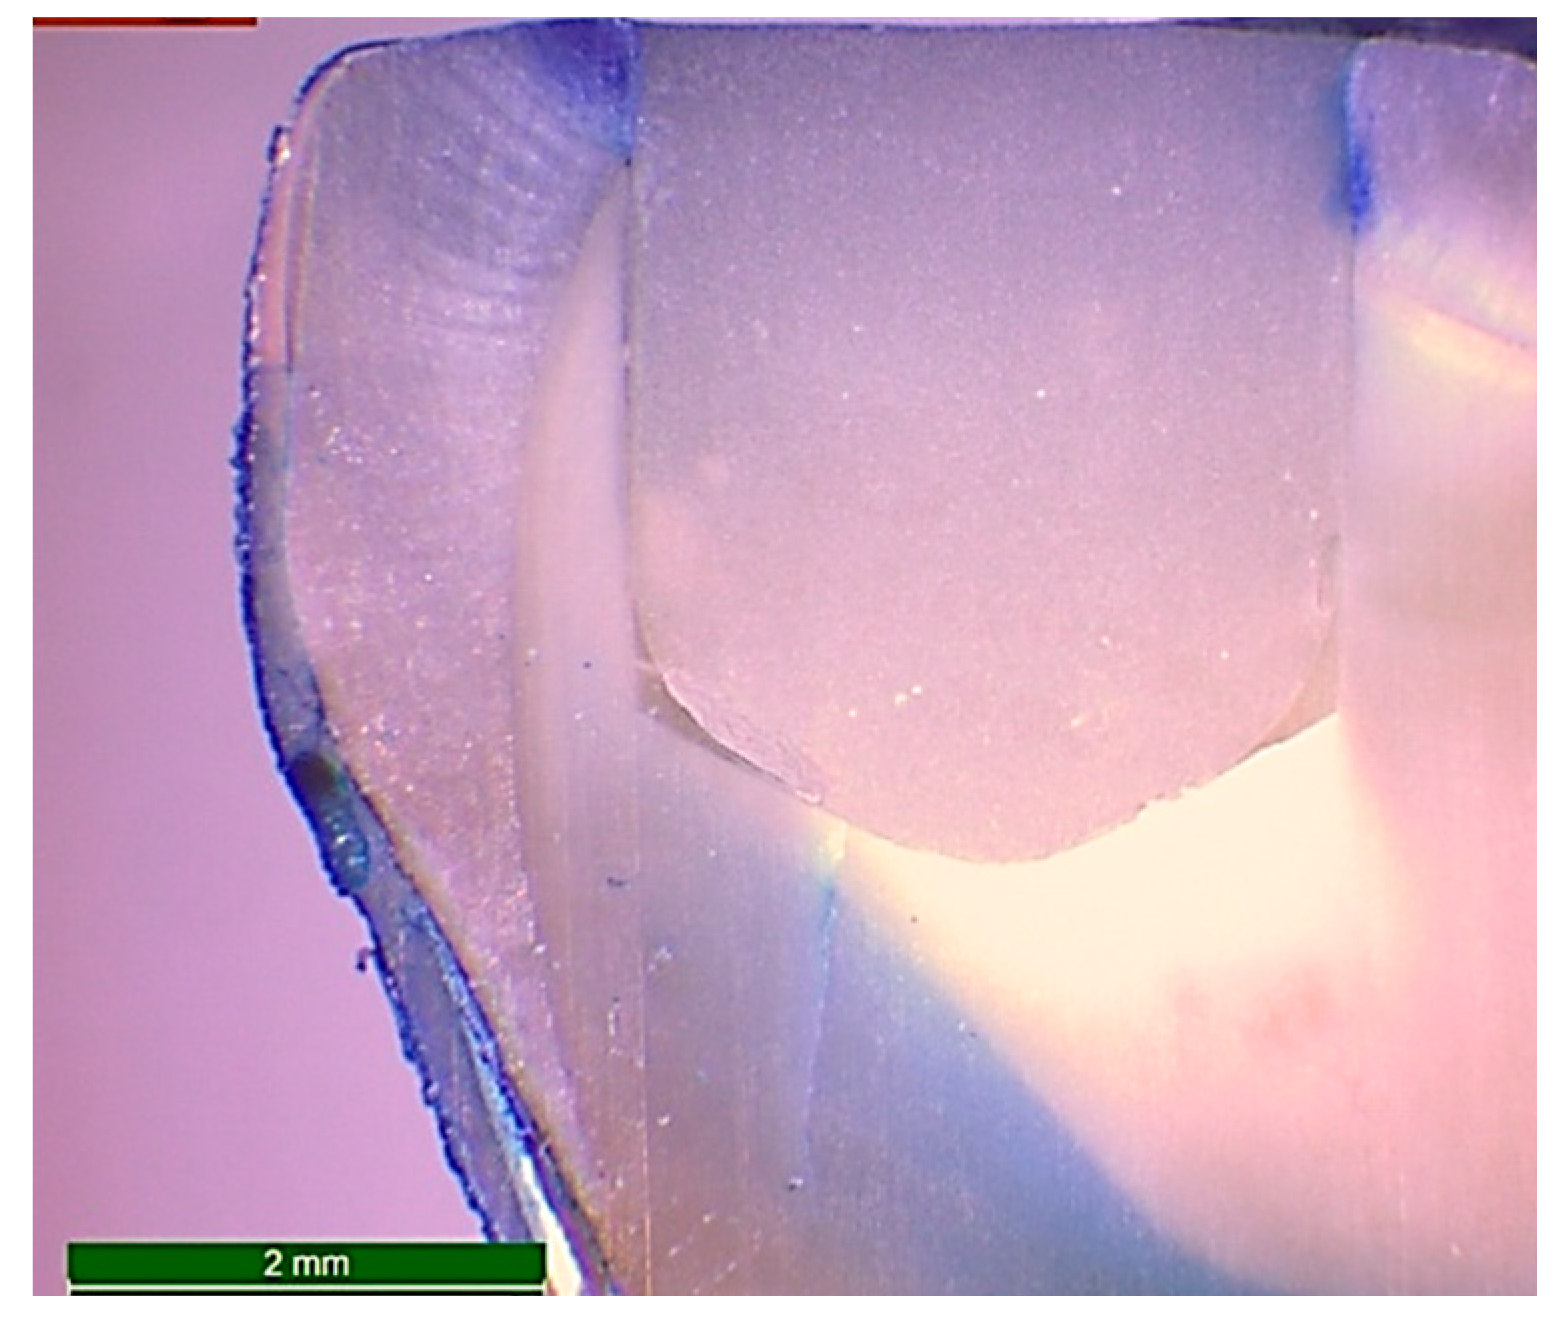

After the packing and curing of the resin composite according to the previously mentioned specimens’ grouping, the surfaces of the restorations were finished and polished using ascending grits (Soflex, 3M OralCare, St. Paul, MN, USA). Prepared specimens for microleakage testing were subjected to cycles of thermal fluctuations for the simulation of artificial aging using a thermocycler (Thermocycler THE-1100, SD Mechatronik, Germany) from 55 (±1) to 5 (±1) °C, with a dwell time of 30 s and a transfer time between each water bath of 10 s—for 5000 cycles. After the completion of thermo-cycling, the teeth were dried and double coated with a waterproof nail varnish along the whole surfaces except for 1 mm around the margins of the restoration. Then, the teeth were immersed in freshly prepared 1.0% methylene blue dye (Certistain, Merck, Darmstadt, Germany) for 24 h. The teeth were then rinsed thoroughly with running water and sectioned buccolingually along their long axes into two sections using an automated water-cooled diamond saw (EXAKT 300 CP Band System, Norderstedt, Germany). The specimens were examined for marginal leakage and dye penetration by using stereomicroscope (Wild Heerbrugg transmitted-light stand EB, Leica microsystem, Wetzlar and Mannheim, Germany) at a magnification of 15X (Figure 3). The scoring of dye penetration was done for marginal leakage (Figure 4) as follows:

Figure 3.

Microphotograph at 15X magnification of a longitudinal section of a restored standardized cavity in a sound molar after 5000 cycles of thermo-cycling and immersion in freshly prepared 1.0% methylene blue dye for 24 h in order to examine the marginal leakage by evaluation of the grade of dye penetration.